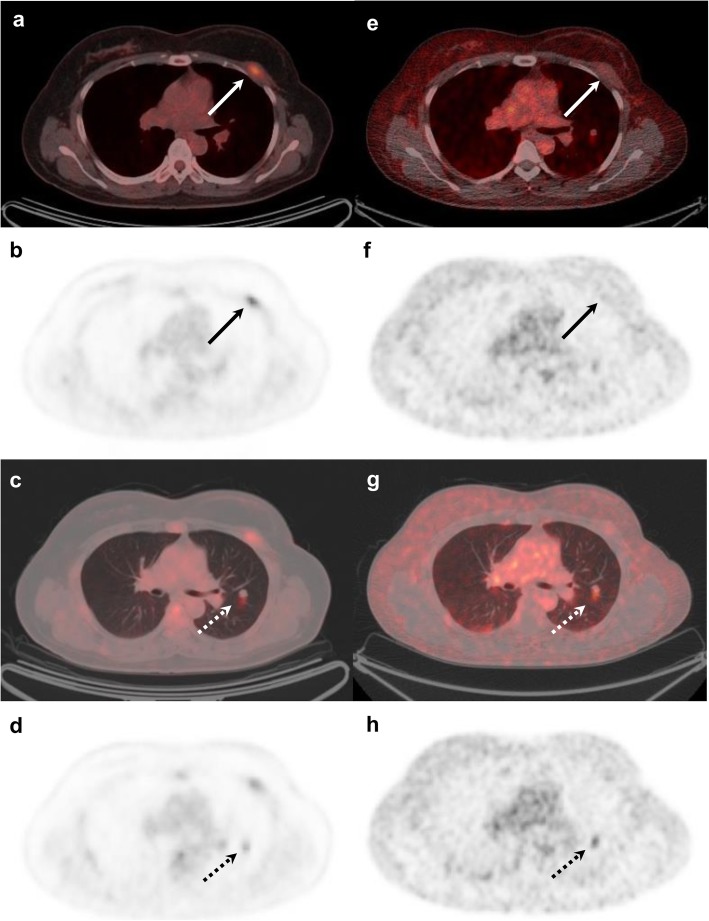

Fig. 3.

[18F]FDG and [18F]FES PET/CT images of a 51-year-old female with histologically confirmed ER-positive recurrence (Allred score 5) in the chest wall. Transaxial [18F]FDG images show positive uptake in the left chest wall recurrence (a, b; arrows). Additional positive [18F]FDG uptake is seen in the left lung (c, d; dotted arrows). By contrast, [18F]FES PET/CT is negative in the chest wall (e, f; arrows) and positive only in the left lung (g, h; dotted arrows). The left lung lesion was later confirmed as ER-positive metastatic breast cancer

Of the 45 patients with recurrent breast cancer, 25 patients (56%) had a total of 47 [18F]FES-positive non-reference lesions (Fig. 2). All these patients had ER-positive reference lesions. These [18F]FES-positive lesions were located in the bone (n = 10), regional lymph nodes (n = 10), distant lymph nodes (n = 11), lung (n = 11), pleura (n = 4), and breast (n = 1). Interestingly, three of nine patients who had ER-positive/[18F]FES-negative reference lesions had [18F]FES-positive non-reference lesions. One non-reference lesion of the three patients was confirmed as ER-positive metastatic breast cancer by histologic analysis (Fig. 3). If these three patients were to be added to the calculation of the sensitivity of [18F]FES, the figure would be 77.8% (35/45, 95% CI, 62.9–88.8).